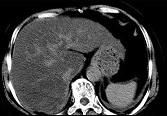

问题 男,32岁,肥胖,常酗酒,肝肋下一横指,肝区轻微压痛,影像表现如图,应诊断为 ( )

选项 A.肝炎 B.肝硬化 C.脂肪肝 D.肝豆状核变性 E.肝含铁血黄素沉着

答案 C